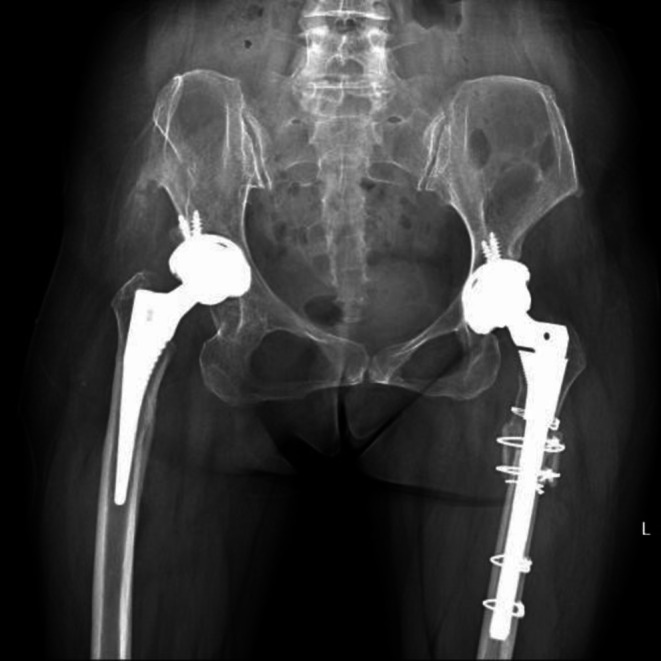

Background: S-ROM prosthesis, one well-used femoral prosthesis in the patients with developmental dysplasia of the hip (DDH), has a skipping size of the distal stem diameter. The purpose of this study was to investigate whether its 2-mm incremental diameter could meet clinical needs for high-riding DDH patients.

Methods: Between July 2018 and December 2022, the Hartofilakidis type C DDH patients with S-ROM stem (9 or 11 mm) were retrospectively enrolled according to the inclusion criteria and exclusion criteria in our institute. The intraoperative femur fractures, the diameter of the femoral medullary cavity, the canal filling ratio of the S-ROM stem, the closure conditions of the stem slot, and the healing rate of subtrochanteric osteotomy were analyzed to evaluate the effect of stem design on clinical outcomes. Statistical analyses were conducted using independent samples t-tests, chi-square test, and logistic regression analysis with a significance threshold of p < 0.05.

Results: A total of 95 patients (109 hips) were included in this study, including 60 hips with 9 mm S-ROM and 49 hips with 11 mm S-ROM. Compared with the 9 mm S-ROM group, the 11 mm S-ROM group presented nearly 5 times the intraoperative fracture rate (16.3%, 3.3%, p < 0.05). The mean diameter of the femoral medullary cavity in the 9 mm S-ROM group was 0.84 ± 0.20 mm and in the 11 mm S-ROM group was 1.03 ± 0.18 mm. The canal filling ratio in the 9 mm S-ROM group is significantly lower than that of the 11 mm S-ROM group. In the 11 mm S-ROM group, the filling ratio of the femoral medullary cavity of fracture hips was significantly higher than that in non-fracture hips.

Conclusion: The S-ROM design with a distal stem diameter increment of every 2 mm would increase the risk of intraoperative periprosthetic femoral fractures in high-riding DDH patients. It is necessary for a 1-mm increment of distal stem diameter in such patients.